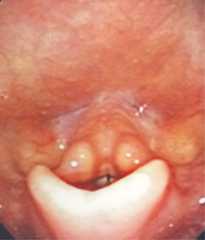

Figure 3.

Follow-up laryngoscopy image showing significant improvement in erythema and swelling.